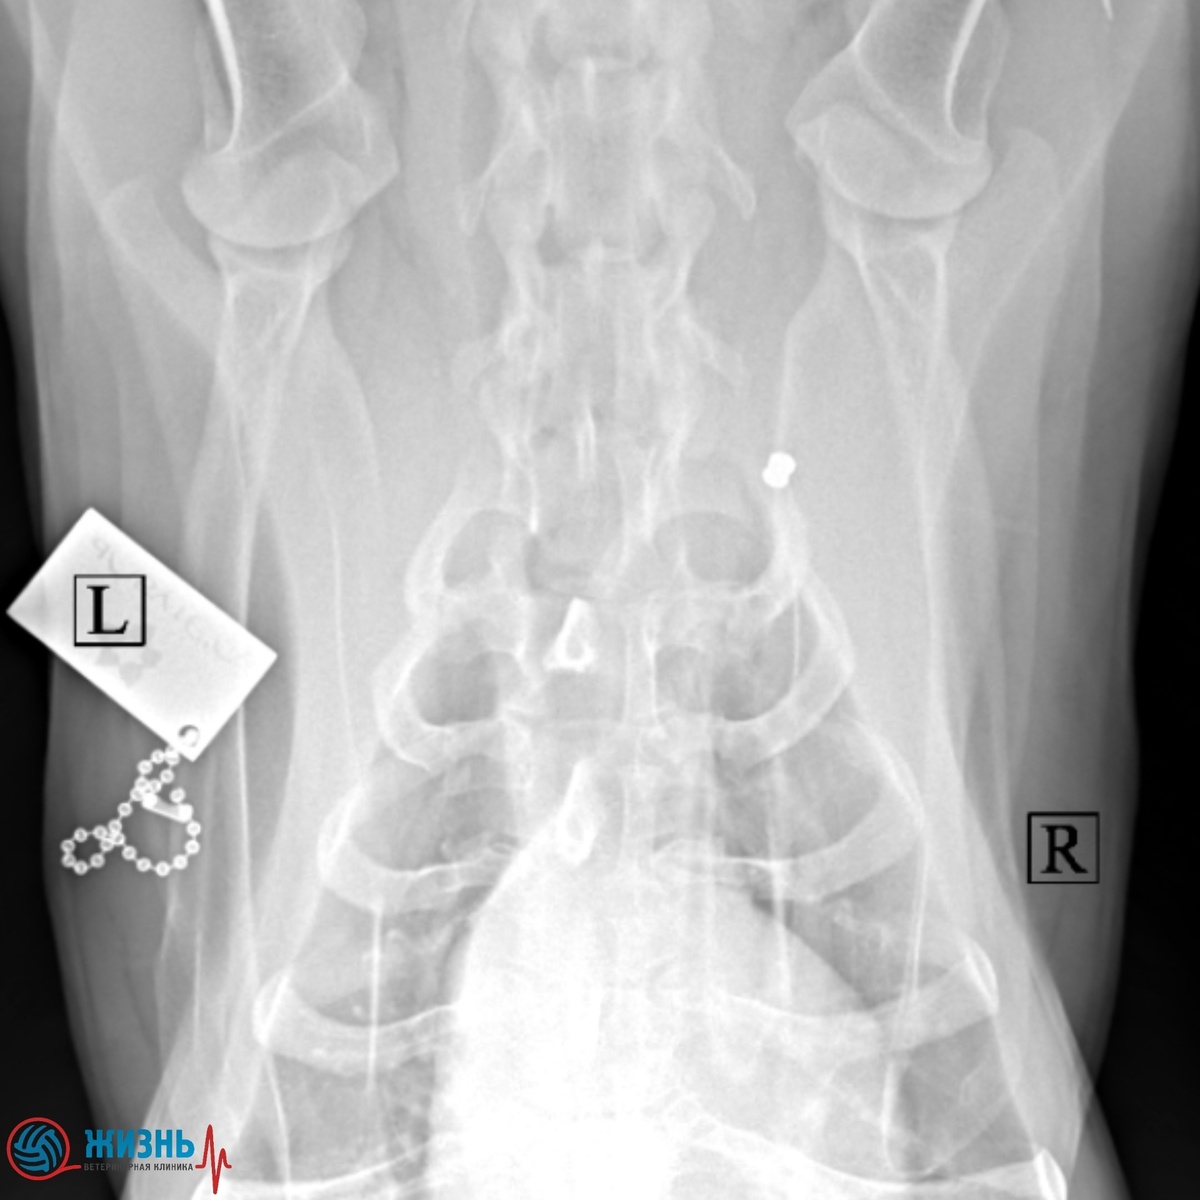

На рентгене мы обнаружили дробь от пневматического оружия в области плечевого сплетения. К счастью, жизненно важные органы не пострадали, и Бу чувствует себя хорошо.

Дробь от воздушки у собаки на рентгене.

Сейчас принято решение не извлекать дробь, так как она не угрожает здоровью и может остаться в тканях без последствий. Пёс под наблюдением, мы контролируем его состояние.